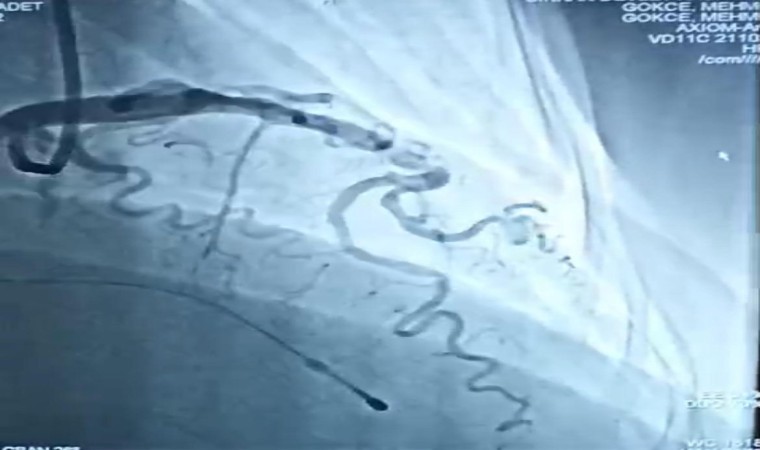

Polikliniğe nefes darlığı başvurusu sonrası yaptıkları incelemede kalp duvarında kalınlaşma tespit ettiklerini belirten Dr. Gökçe, "Kalp duvarındaki kalınlaşma sonrası ilaç tedavisi başladık. Ancak etkili bir sonuç alamayınca hastamıza kalınlaşan kalp duvarını inceltmek için alkol ile yakma işlemi yaptık. Hastamızın özellikle damarlarında zorlu bir işlemi vardı. Daha önce üst merkezlerde, üniversite hastanelerinde yapılan bir işlemi burada zorlu da olsa başarılı bir şekilde işlemimizi gerçekleştirdik. Hastamıza öncelikle anjiyoya alarak normal anjiyografik yöntemler ile kalp damarına ulaştıktan sonra, kalınlaşma yapan damara ulaştıktan sonra, o damara saf alkol vererek inceltip daha sonra nefes darlıklarını özellikle iki haftadan sonrada hastamızın belirgin düzelmesini bekliyoruz. Takibinde de hastamıza iki gün yoğun bakım takibi ve bir günde serviste takibinden sonra da yarın rahat bir şekilde ve şikayetsiz bir şekilde hastamızı taburcu etmeyi planlıyoruz” dedi.